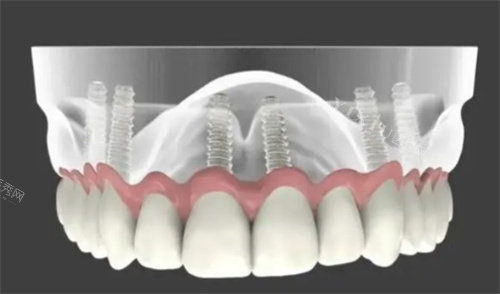

接诊我的是种植科黄自印医生,他戴着金丝眼镜,说话时总带着温和的笑意。不同于其他医生直接推荐方案,黄医生先让我躺上检查椅,用3D口扫仪为我做了全口扫描。“您看,您的牙槽骨条件不错,但缺牙区邻牙有轻微倾斜,建议先做牙周基础治疗再种牙。”他指着屏幕上的三维模型,像讲解PPT一样耐心解释每个步骤,连“种植体植入后需要3-6个月骨结合”这种术语都换成了“就像种树一样,得等根系扎稳”的比喻。

手术过程比预期顺利得多。黄医生先在牙龈上开了个小口,用导航仪精细定位种植点,我能感觉到钻头在骨头上轻轻震动,但完全没有想象中的剧痛。护士每隔几分钟就轻声报时:“还有10分钟就完成啦!”当听到“手术结束”的瞬间,我甚至有点恍惚——这就完了?